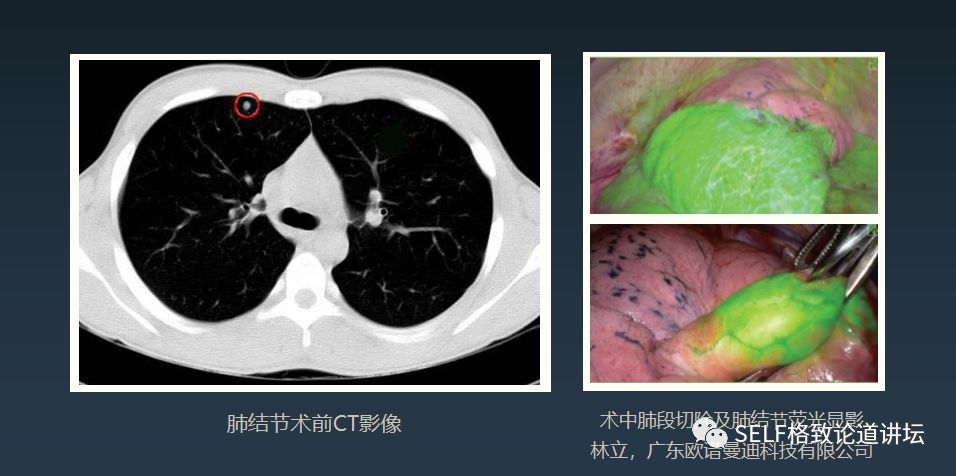

第二个故事,几年前,我去参观一台机器人做的手术。当时这个患者有一个肺部结节,手术前,医生通过一些染料在患者身体的结节周围打了一圈标记。

但是在手术过程中这些标记找不到了,最后通过医生丰富的经验去判断,还是艰难地找到了标记。

这反映了一个问题,即便你的手很灵巧,但如果你的眼睛看不到组织表面以下的这些病变,还是做不好手术的,手术依然困难。

随着技术的进步,也为手术机器人带来了一些突破。像图中就是用一种染色的办法,通过荧光成像,把它的图采集回来,这样手术机器人就可以看到病变在哪里。

这是肿瘤的剥离视频。在手术过程中,我们可以看到哪个地方需要做手术,非常明显。

当然还有另外一种技术,就是增强现实技术。我们在术前可以通过CT、超声诊断出一些病变,把它三维呈现出来,并且在三维图像上能够找到这些病变组织,包括一些血管,然后再叠加到我们的手术过程中。

它让机器人知道什么地方可以做手术,什么地方不能做手术,规避一些像血管、神经等功能性的、风险非常高的部位。机器人技术是对人的眼睛做了一个扩展。